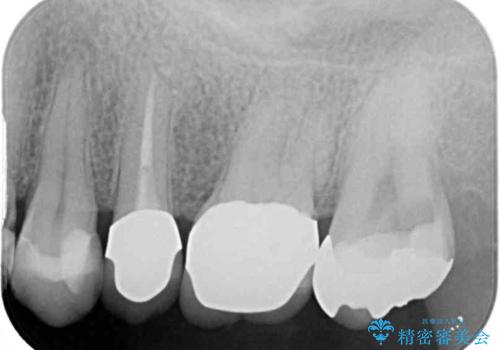

診査をしたところ、レントゲン写真よりとても大きなむし歯があることが分かりました。

虫歯が歯髄腔(神経の部屋)に達している可能性が非常に高かったため、炎症を起こしている神経組織を部分的に切除し、歯根部分の神経組織を保存する治療法が望ましいと考えられました。

処置開始前から神経組織を部分的に除去する可能性が高いことが分かっていたため、ラバーダムなどの環境を整え、無菌的環境下にて処置を進めて行きました。

虫歯は深くまで進行しており、歯冠部の神経から出血が認められました。神経を部分的に除去したところ出血が治まったので、生体親和性の非常に高いセメントにて充填し、仮封をしました。